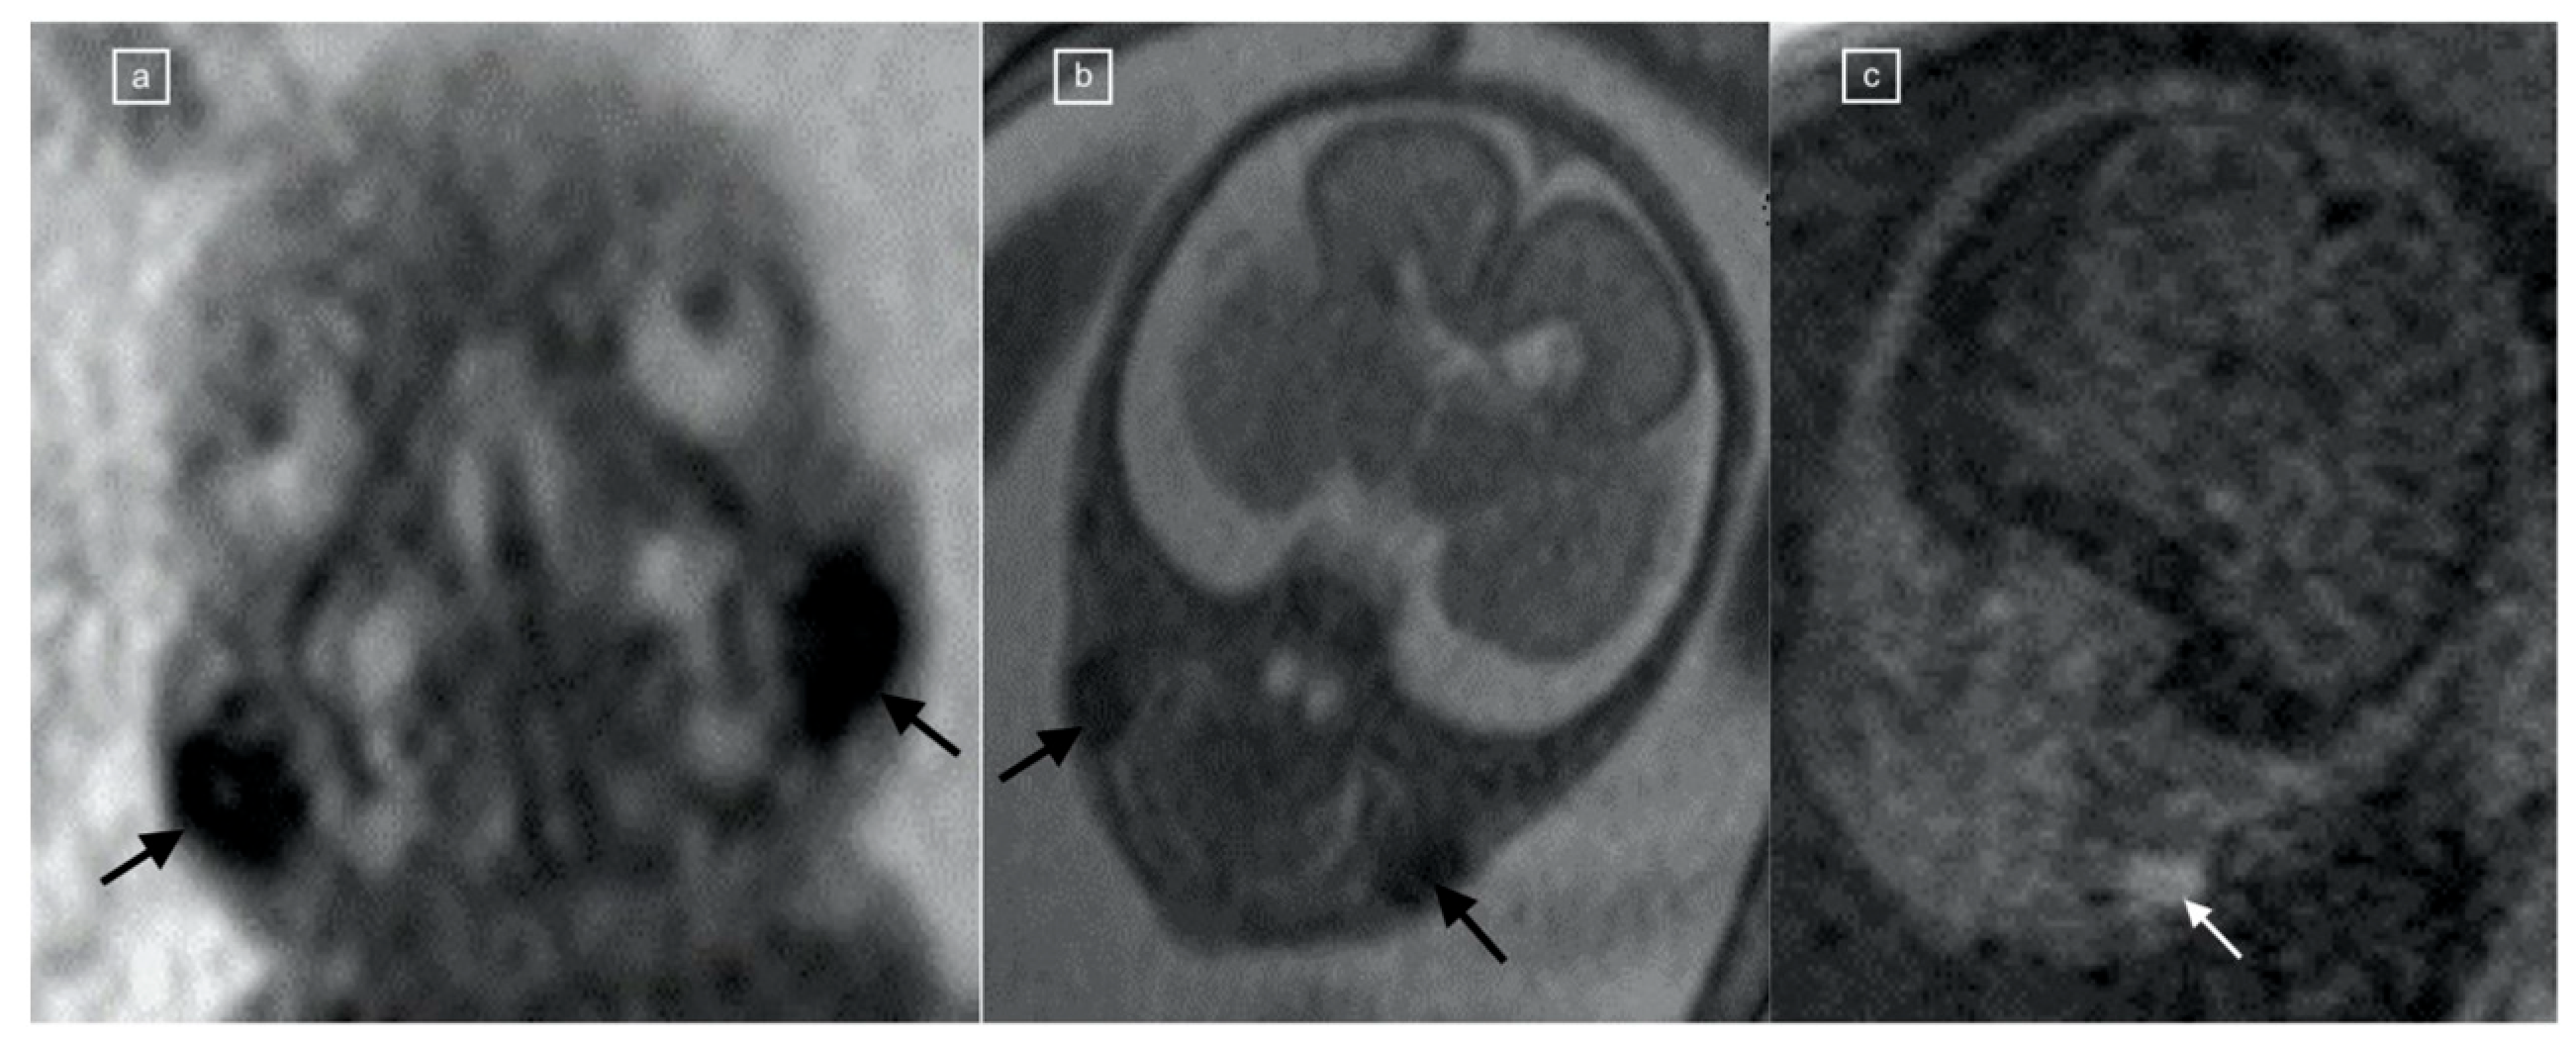

Figure 2. (a,b) Coronal TRUFI MRI in a 23-week fetus, one of dichorionic diamniotic twins, demonstrating bilateral symmetric, oval low-signal-intensity fat pads (black arrows) corresponding to (c) T1 VIBE hyperintensity (white arrow).